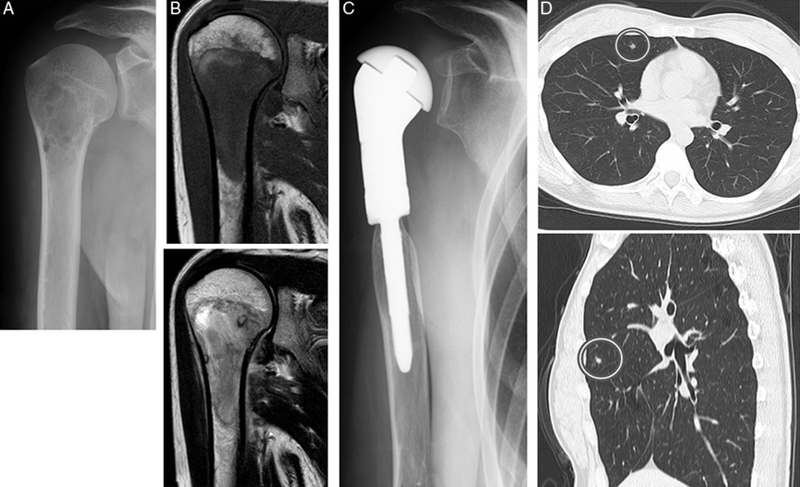

• Chẩn đoán hình ảnh: Chụp X-quang, quét CAT (chụp CT), chụp cắt lớp phát xạ Positron (quét PET), chụp cộng hưởng từ (MRI).